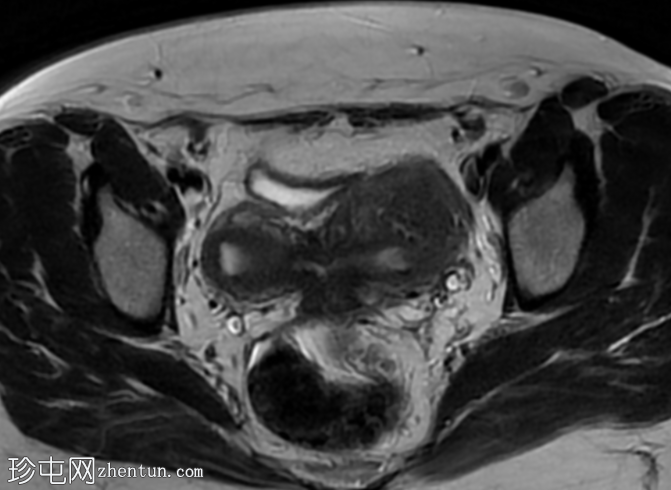

轴位

T2加权像

5.png

双角子宫,有两个子宫角和一个宫颈(单颈双角子宫)

右角正常,分区解剖结构正常,无肌层病变

左角局灶性前壁腺肌症,前壁交界区边界不清,肌层内可见多个高信号灶

两个小的间质性肌瘤和一个大的浆膜下肌瘤

该病例表现为双角子宫单宫颈(双角单颈子宫),左侧单侧局灶性子宫角腺肌症,以及多发性子宫肌瘤。